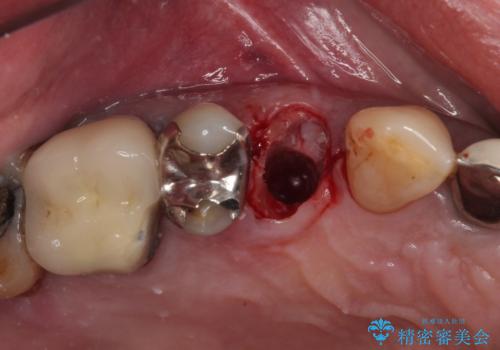

当院での根管治療および歯周外科治療を併用した保存療法、並びに1DAYインプラントによる短期間インプラント治療の双方をご説明し、即日でインプラント治療を選択されました。

仮歯を用意した上で、抜歯即時埋入・即時荷重インプラントによる補綴治療を行うこととしました。

従来のインプラント治療について回った3回の外科手術や半年移動の治療期間とは無縁の、短期間治療を達成することができました。